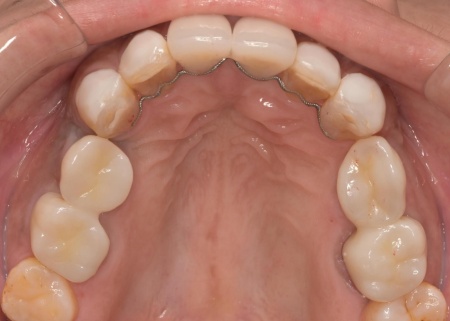

治療後

矯正期間終了後は、被せ物による治療に移行します。

上顎の前歯2本ずつと奥歯4本(左右中切歯・第2小臼歯・第1大臼歯)、下顎の奥歯7本(左第1小臼歯・左右第2小臼歯・第1大臼歯・第2大臼歯)には、見た目が自然なセラミックの被せ物「ジルコニアクラウン」を装着しました。

ジルコニアは、金属を使わないため金属アレルギーの心配が少ない点、人工ダイヤモンドと呼ばれるほどの強度をもち噛む力の強い奥歯にも適している点がメリットです。

加えて、上前歯4本(左右側切歯・犬歯)と下前歯5本(左右中切歯・側切歯・右下犬歯)は、ダイレクトクラウンによる修復を行いました。

ダイレクトクラウンとは、レジン(樹脂)を用いて直接歯の形を作り上げていく治療方法です。

歯を削る量が少ない、色や形を細かく調整しながら仕上げられる、治療後は必要に応じて微調整がしやすいなどのメリットがあります。

最後に、見た目や噛み合わせに問題がないかを確認し、治療を終了しました。